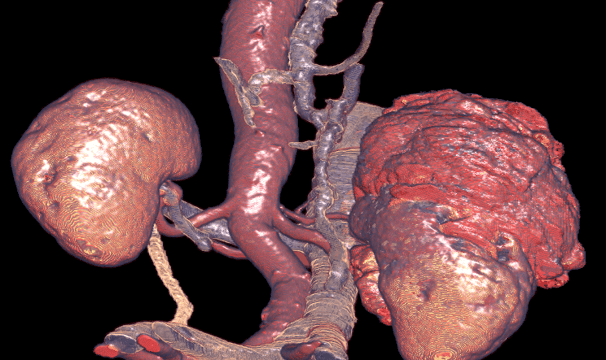

Powered by AI-driven robotics, AIVR.4D robotics transforms conventional 2D scans into 4D color-augmented visuals, unlocking previously unseen diagnostic data in real time.

- Convert 2D CT scans into real-time 4D color visuals.

- Highlight organs, vessels, and tumors with 98% clarity.

AIVR.4D converts standard 2D CT scans into real-time 4D color visuals, delivering a dynamic, high-resolution view of internal anatomy for enhanced diagnostic and surgical accuracy.

The AIVR.4D Robotics System successfully detected cancer thrombi and tumor invasion along the wall of the Inferior Vena Cava (IVC)—a complex and often overlooked diagnostic challenge with conventional 2D CT imaging.

AIVR.4D pinpoints critical invasion sites—such as tumor spread along the Inferior Vena Cava (IVC)—by highlighting organs, vessels, and tumors with 98% clarity.